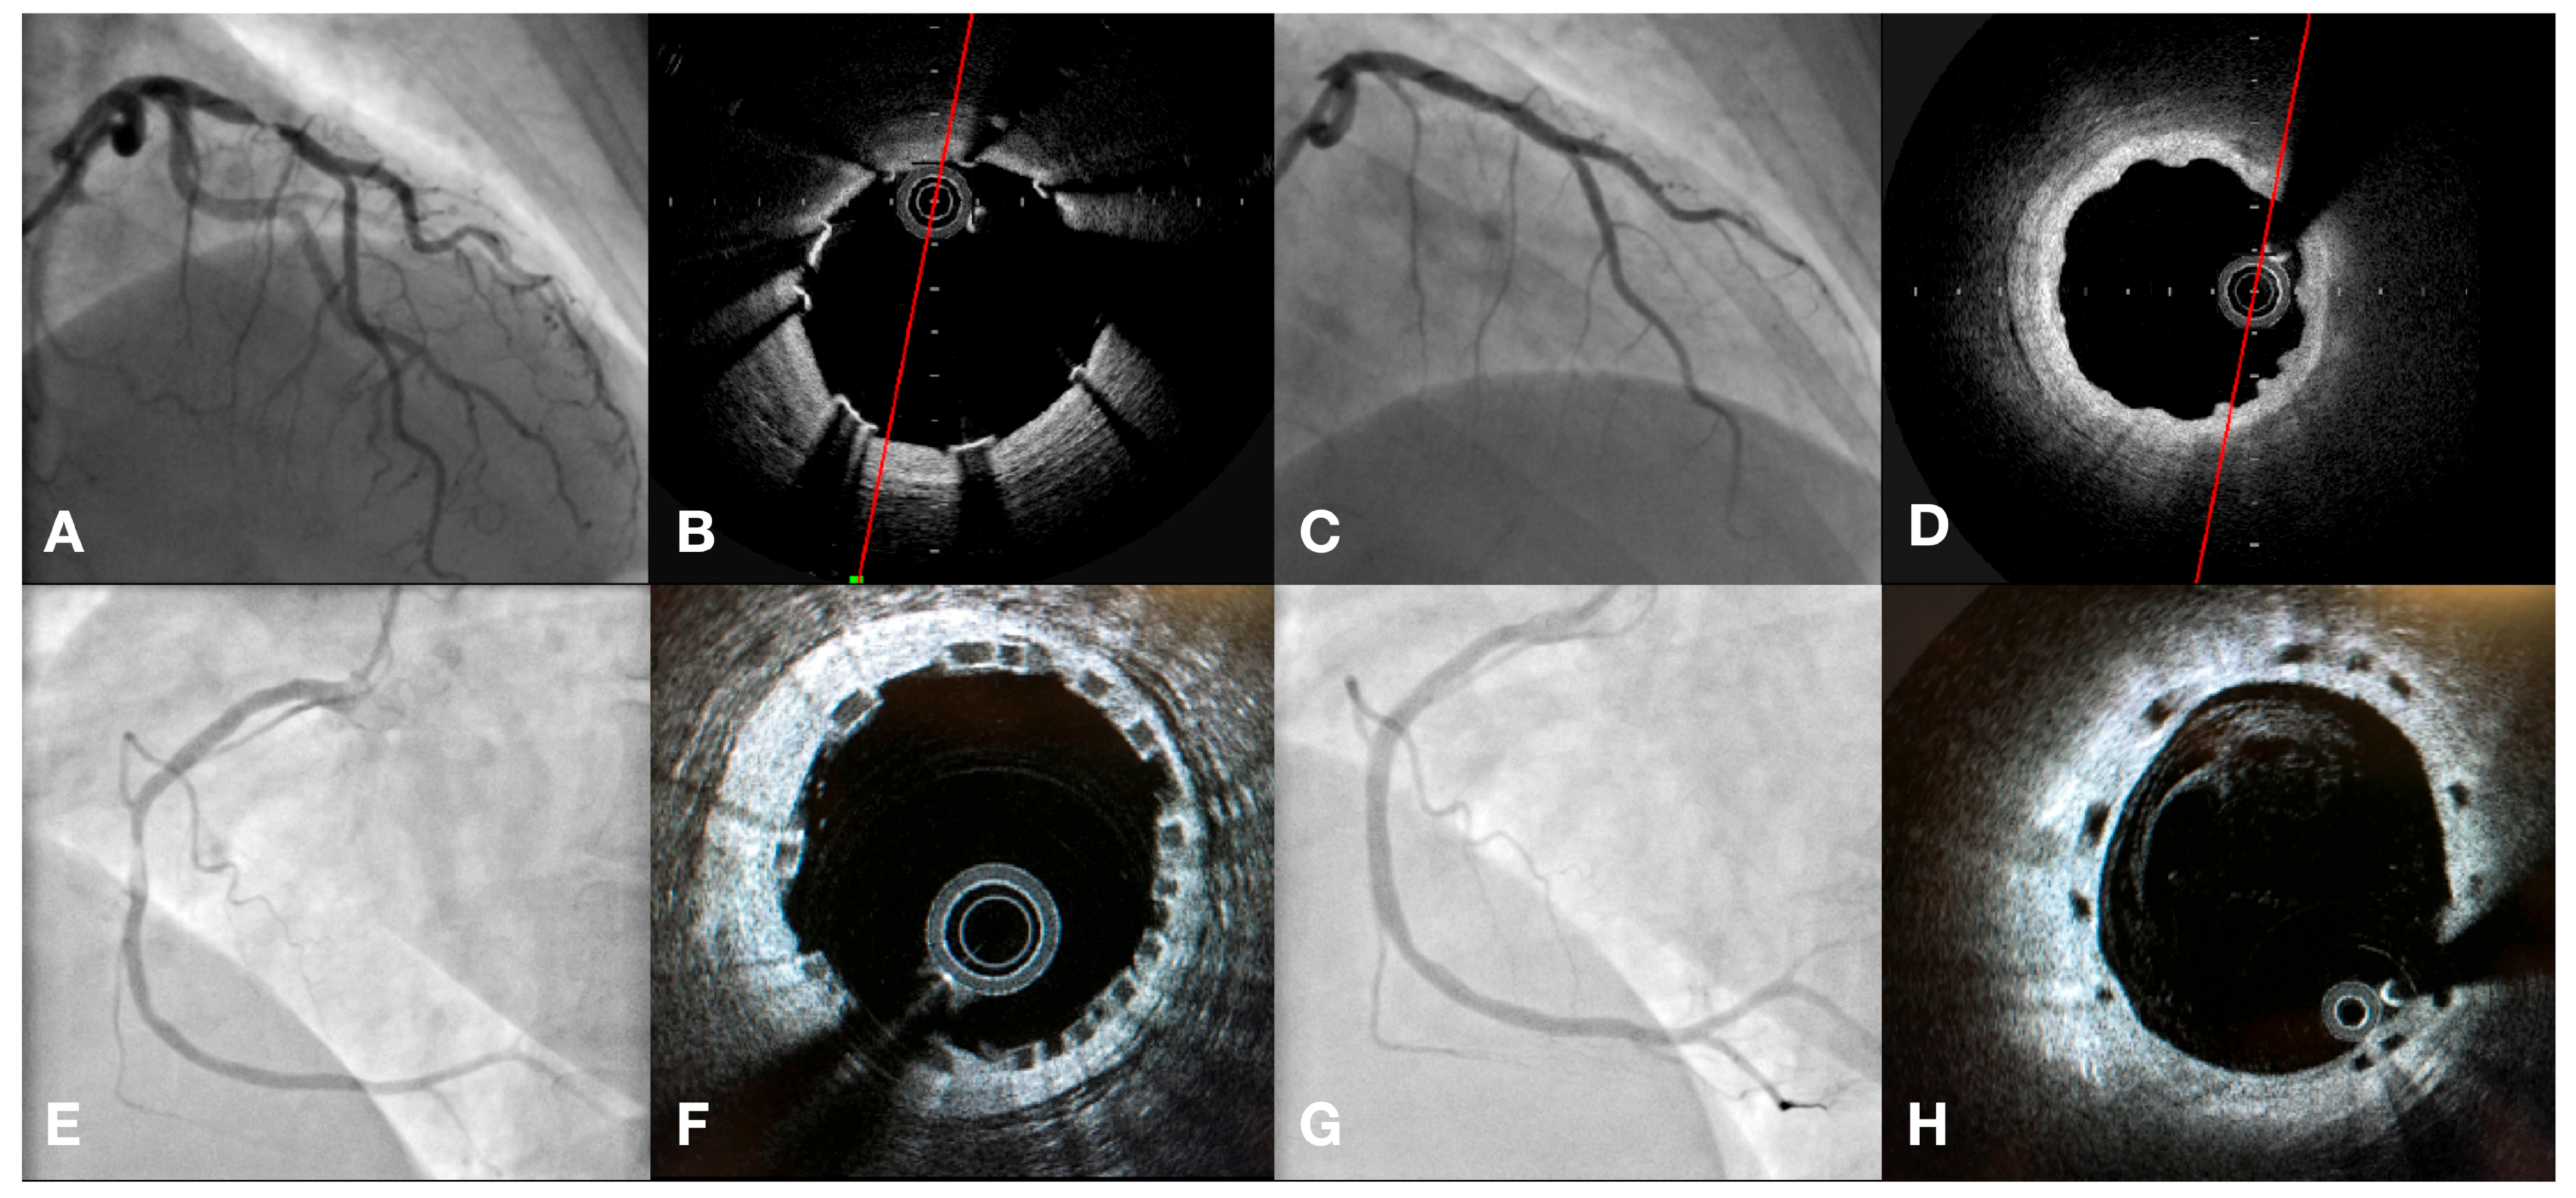

| IVUS/OCT-guided PCI | 41 (21.2%) | 21 (13.1%) | p = 0.052 |